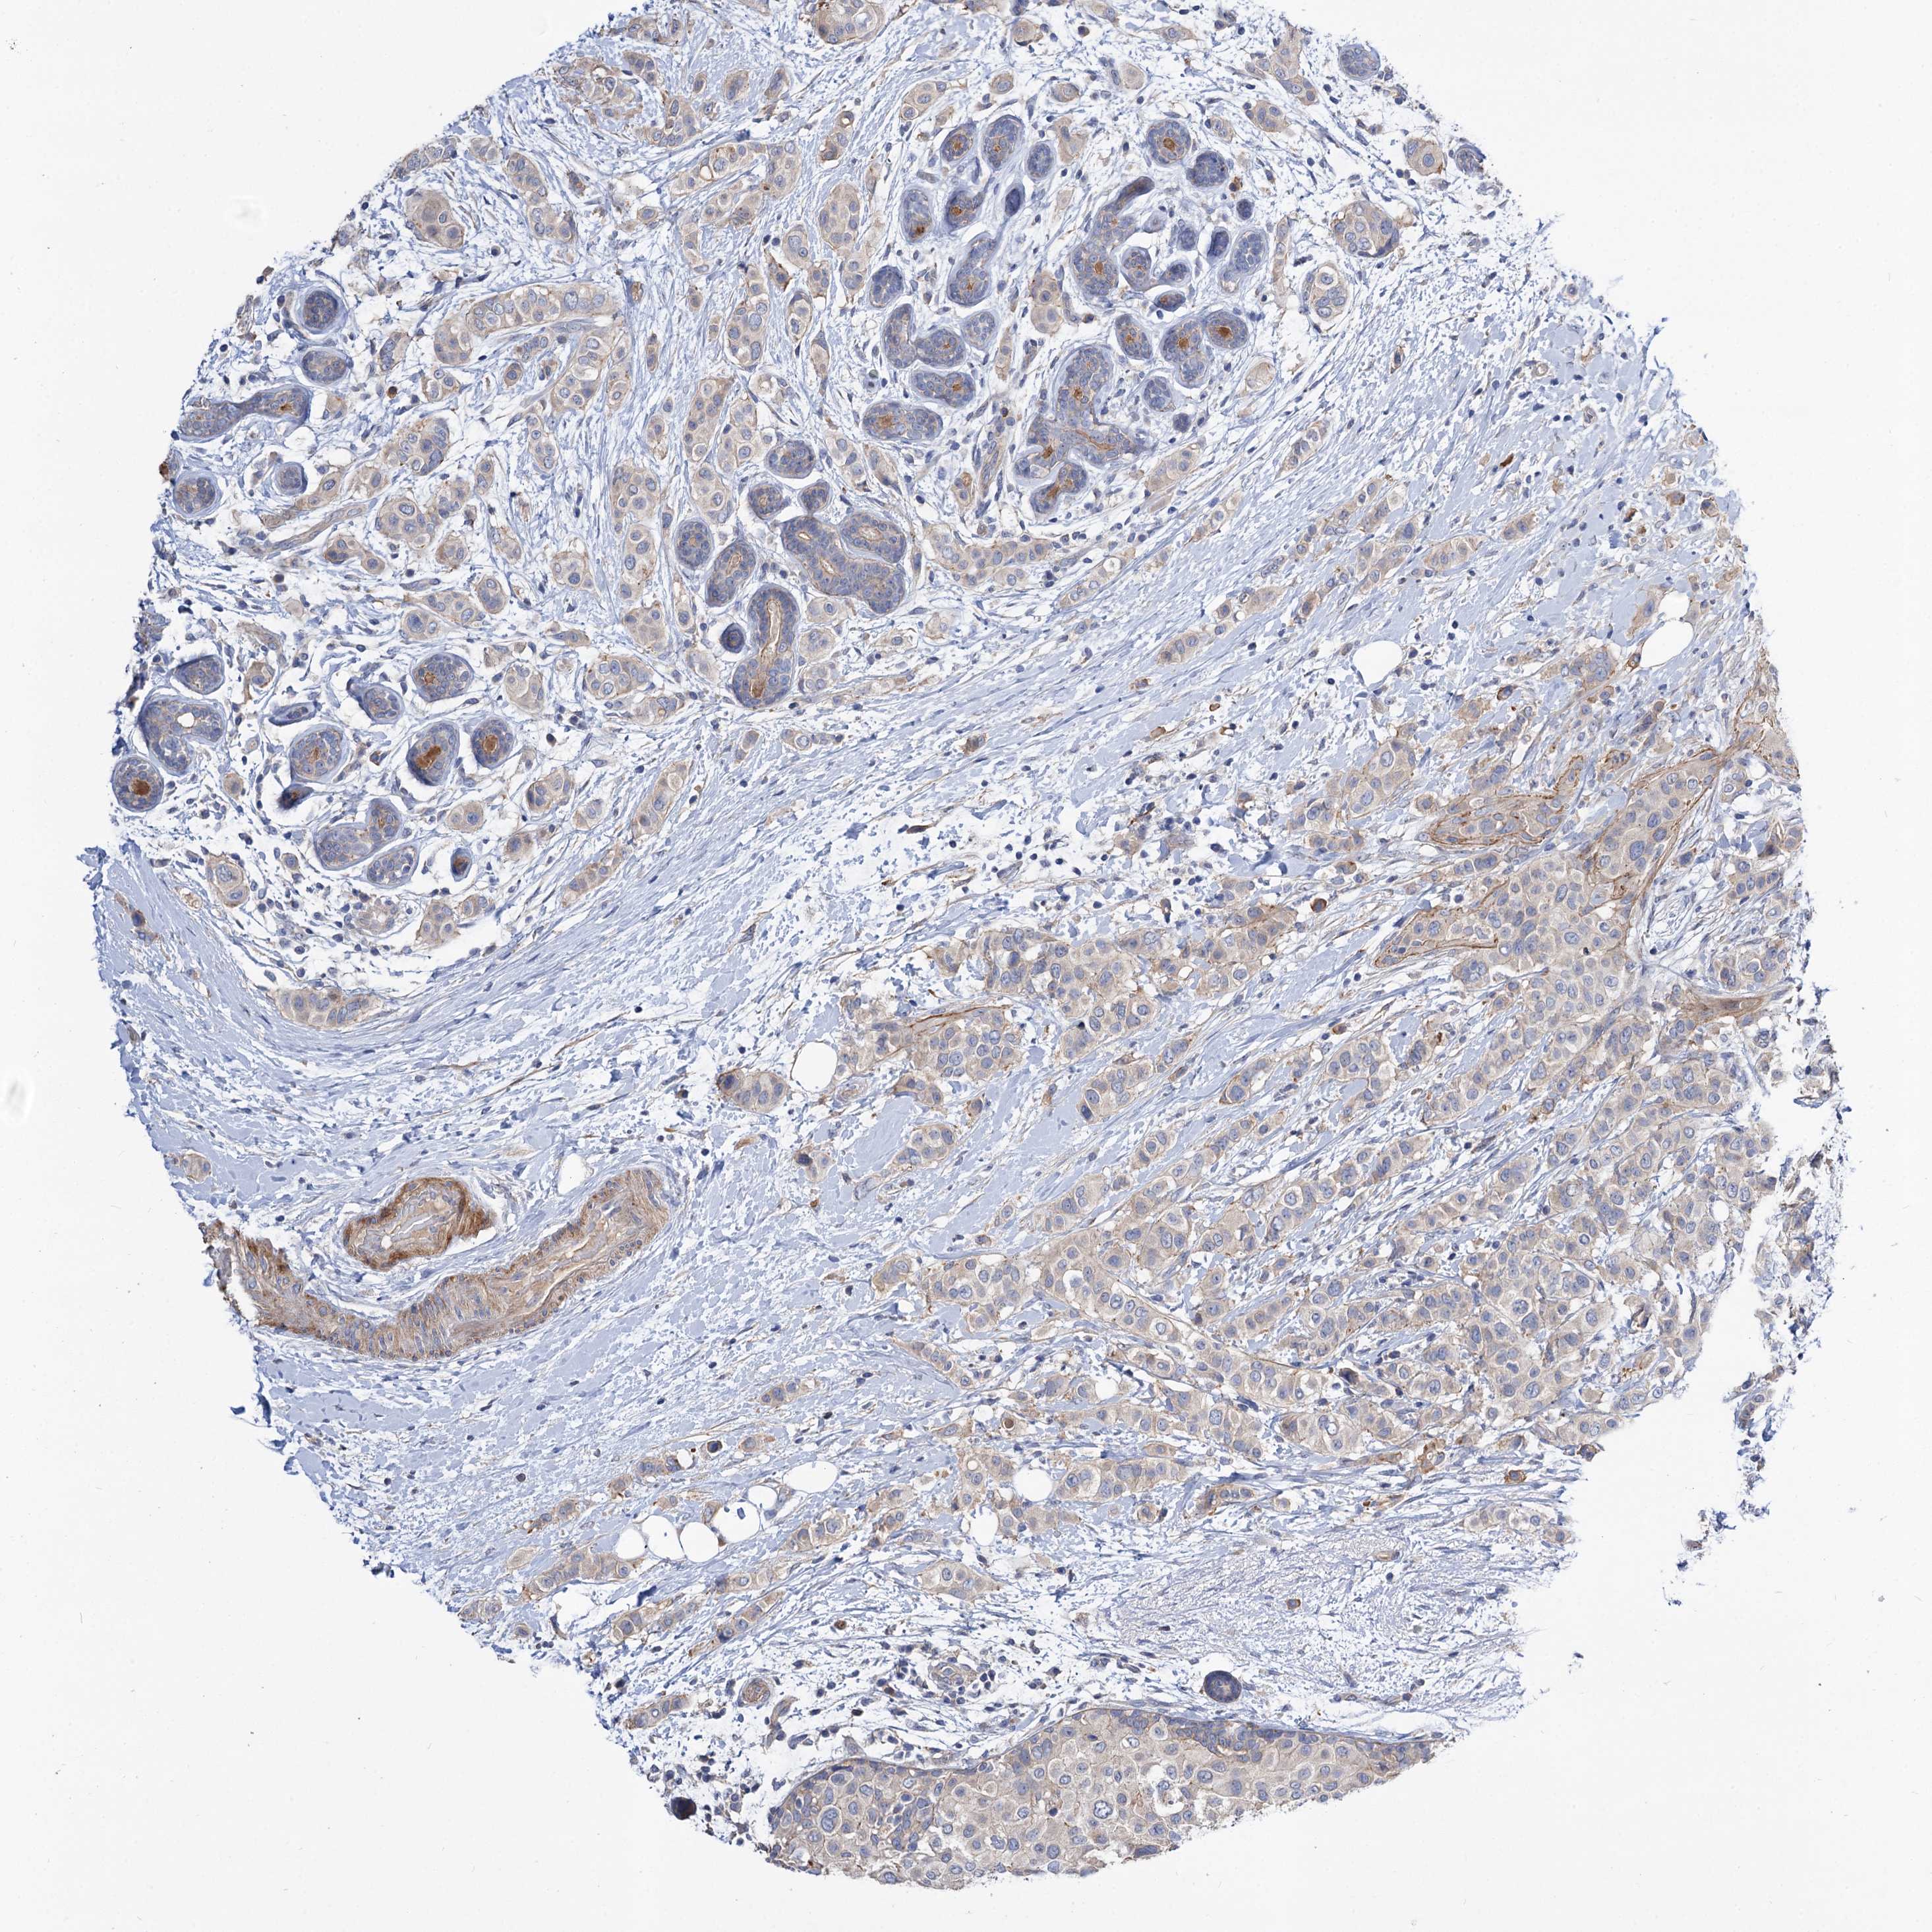

CANCER BREAST CANCER Show tissue menu

BRCA TCGA BRCA VALIDATION PROTEIN EXPRESSION